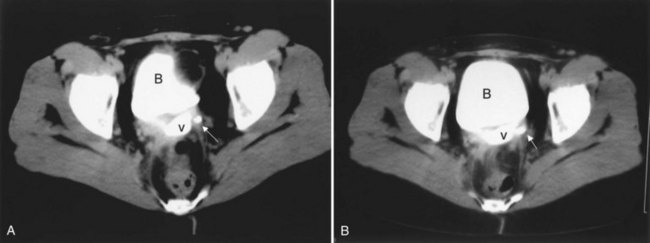

In addition to contrast cystography and VCUG, CT, ultrasonography, and magnetic resonance imaging (MRI) have been used in the evaluation of VVF (Kuhlman and Fishman, 1990; Outwater and Schiebler, 1993; Yang et al, 1994). Delayed CT visualization of contrast within the vagina is considered highly suspicious for VVF in the majority of cases (Kuhlman and Fishman, 1990) (Fig. 77–10). In cases of suspected VVF, CT should be performed with only intravenous contrast, or, alternatively, a CT cystogram can be performed to isolate the bladder. A vaginal tampon placed per vagina during IVU or CT scan may improve the sensitivity for finding small or occult VVF in patients with an otherwise negative evaluation (Wesolowski and Meaney, 1977). Cross-sectional imaging may also be helpful in assessing for recurrent malignant disease in those with such a history.

Figure 77–10 CT scan of vesicovaginal fistula (VVF). A, After intravenous administration of the contrast agent, there is high-density material in both the bladder and vagina consistent with a VVF. The fistulous connection between the bladder anteriorly and the vagina posteriorly. B, Sagittal CT reconstruction demonstrating VVF.